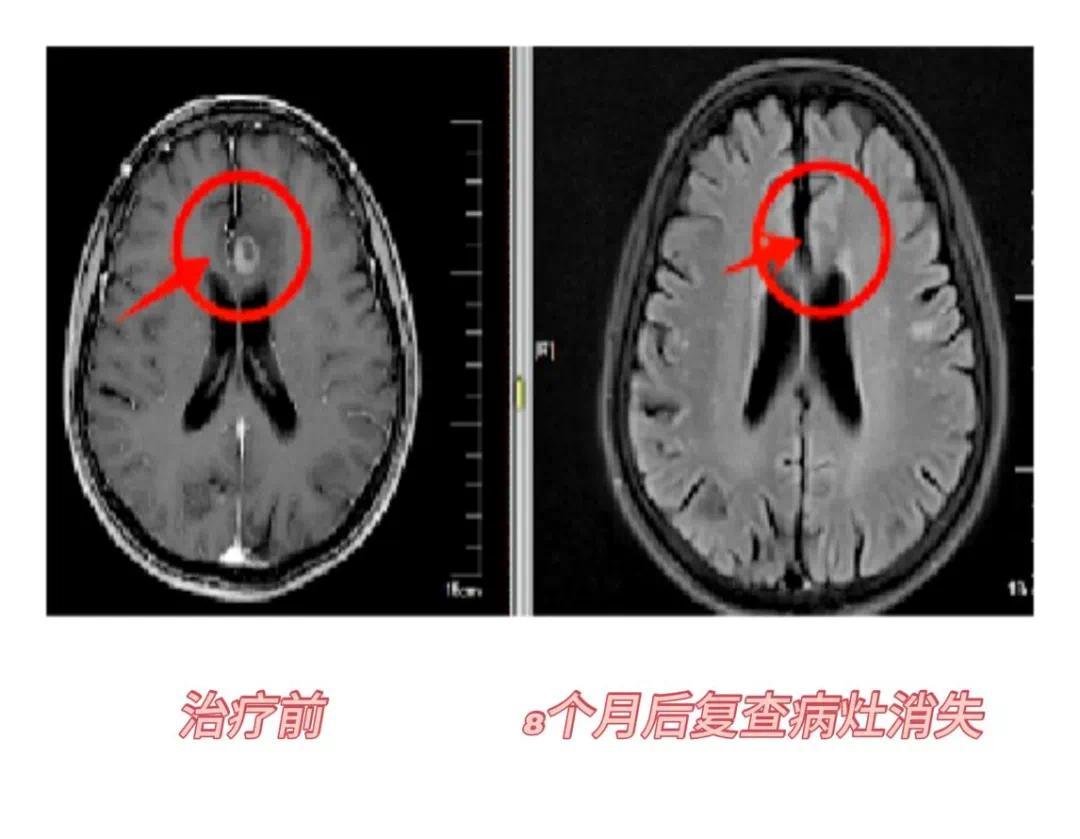

射波刀脑部病例:患者老年女性,82岁,小脑继发恶性肿瘤,综合因年龄和身体状况等因素不适合进行手术,选择行射波刀治疗7次,治疗完复查病灶失去活性,8个月后复查病灶消失。